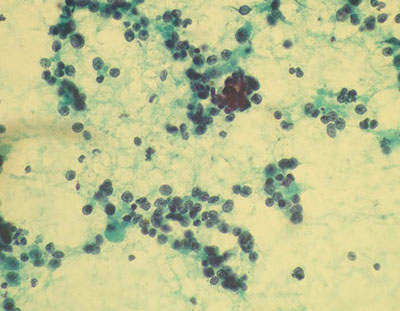

Sialadenosis

-Refers to nonneoplastic noninflammatory swelling in association with acinar hypertrophy and ductal atrophy. Usually bilateral parotid gland involvement

-Aspirates appear normal except acinar cells are significantly larger than normal and inflammatory cells tend to be absent.